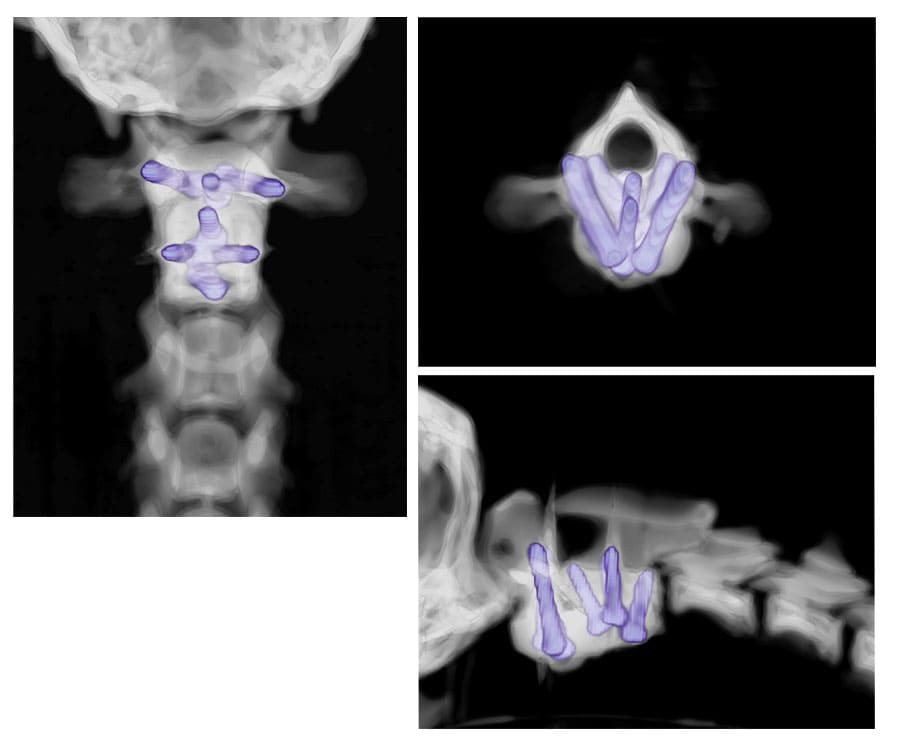

[The bones need to be stabilized with screws, but they are tiny and drilling in the wrong place could be catastrophic! (1a, 1b)]

[We plan exactly where we want the screws to go (2a), exactly what size they should be (2b), and exactly what angles they should be at (2c).]

[We then use CT to check the implants are in the correct place (4a), do not impinge on the spinal canal (4b) and that the bones are in the correct position (4c).]